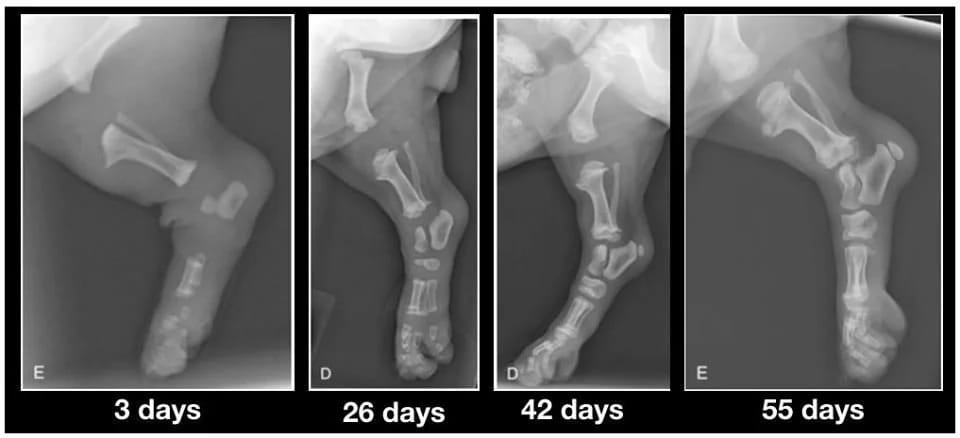

When you finally welcome your 10 week old puppies, please keep this image in mind. Their bones aren’t even touching yet. They walk so beautifully with big floppy legs and wobbly movements because their joints are made entirely of cartilage, muscles, tendons and ligaments covered in skin. Nothing fits properly or has any real grip yet.

When you run them excessively or don’t limit their exercise to keep them from doing too much during this time, you’re not giving them the chance to grow properly. Each big jump or bounding and excited run causes impacts between the bones.

In reasonable quantities, this is not problematic and it is normal wear and tear that will occur.

But when you let the puppy jump off the couch or bed, take him for long walks, you damage this forming joint. When you let the puppy move on slippery tiles, you damage the joint.